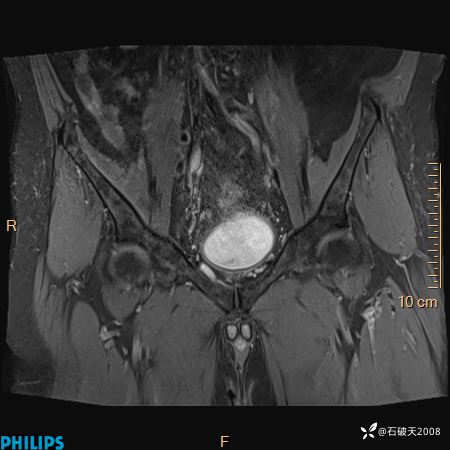

2023年3月份MRI影像

T2压脂冠状位